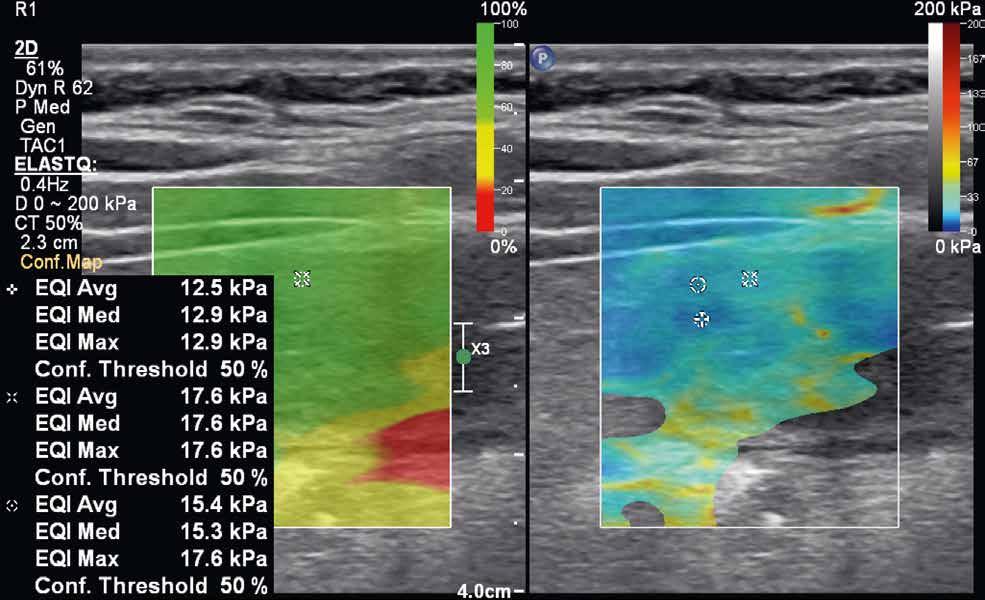

rychlost na hodnoty tlaku v kilopascalech. Výsledná informace je opět kódována do barevné mapy (v klasickém B-obraze), zachycující škálu tuhosti vyšetřované tkáně. Tranzientní elastografie využívá k vyslání pulzu mechanických vibrací sondy, bodová shear-wave elastografie využívá výše popisovanou techniku ARFI ke generování pulzu do jednoho bodu. Nevýhodou tranzientní elastografie je absence klasického B-módu, a tedy nemožnost morfologického zhodnocení vyšetřované tkáně. Nejnovější technikou je 2D shear-wave elastografie (obr. 4–7). Iniciálně je v krátkém časovém intervalu vysláno několik akustických pulzů, následovaných vznikem střihových vln ve více bodech. Výhodou této techniky je možnost sledovat tuhost tkáně v reálném čase. Některé moderní přístroje využívající 2D shear-wave elastografii mají nástroj označovaný „confidence map“. Mapa se zobrazí ve druhém okně na displeji přístroje a pomocí barevné škály hodnotí úroveň, s jakou se v daném místě propagují střihové vlny. Na základě těchto informací pak může vyšetřující zvolit optimální místo k měření tuhosti tkáně.

Obr. 4–7: Elastografie. U pacienta s Crohnovou nemocí ve fázi aktivního zánětu vidíme edematózní stěnu s prosáknutím a uzlinami v okolí (5). Elastograficky je stěna „měkčí“ (4) ve srovnání s pacientem s chronickou fází onemocnění (6, 7), u kterého je stěna fibrózně změněná.